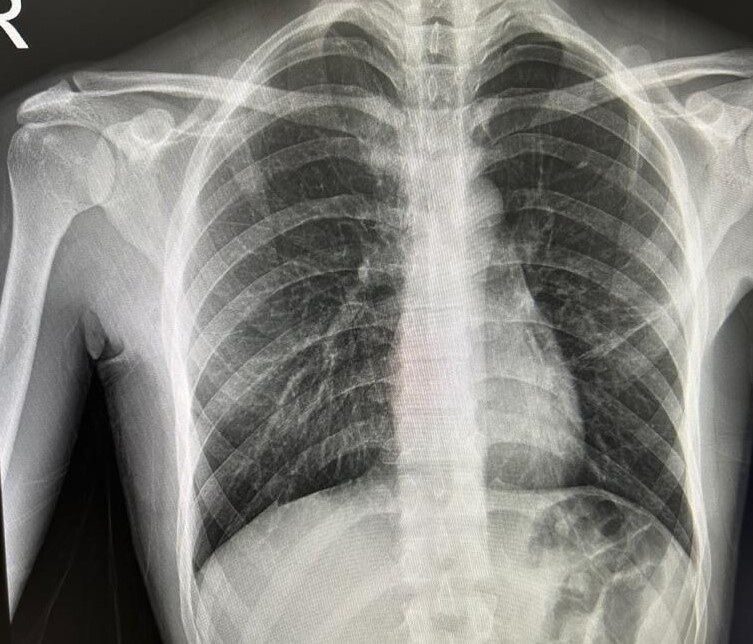

Bayburt’ta nefes darlığı şikayetiyle acil servise başvuran ve daha önce de spontan pnömotoraks (akciğer sönmesi) öyküsü bulunan bir hasta, Göğüs Cerrahisi Uzmanı Op. Dr. Halil Kolcu tarafından yapılan başarılı müdahaleyle sağlığına kavuştu.

Yeniden akciğer sönmesi tanısı konulan hastaya, Op. Dr. Halil Kolcu tarafından 3 santimetrelik tek kesiyle kapalı olarak cerrahi tedavi uygulandı. Bilinci açık ve uyanık bir şekilde işlem uygulanan hasta, başarılı geçen operasyonun ardından aynı gün içerisinde taburcu edildi. Yapılan cerrahi müdahale ile hastanın sağlığına kavuştuğu öğrenildi.